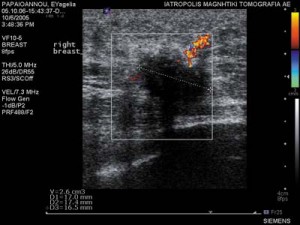

Οι Υπέρηχοι υψηλής ευκρίνειας είναι μέθοδος που δεν χρησιμοποιεί ακτινοβολία και επιτρέπει στα χέρια έμπειρου απεικονιστή να λύσει προβλήματα που αφορούν:

H Υπερηχητική Μαστογραφία είναι η εξέταση εκλογής σε νεαρές γυναίκες μικρότερες των 30 ετών και αποτελούν συμπληρωματική εξέταση σε γυναίκες με πυκνούς μαστογραφικά μαστούς.

Κατευθύνουν με ακρίβεια βιοψίες βλαβών που απεικονίζονται υπερηχοτομογραφικά.